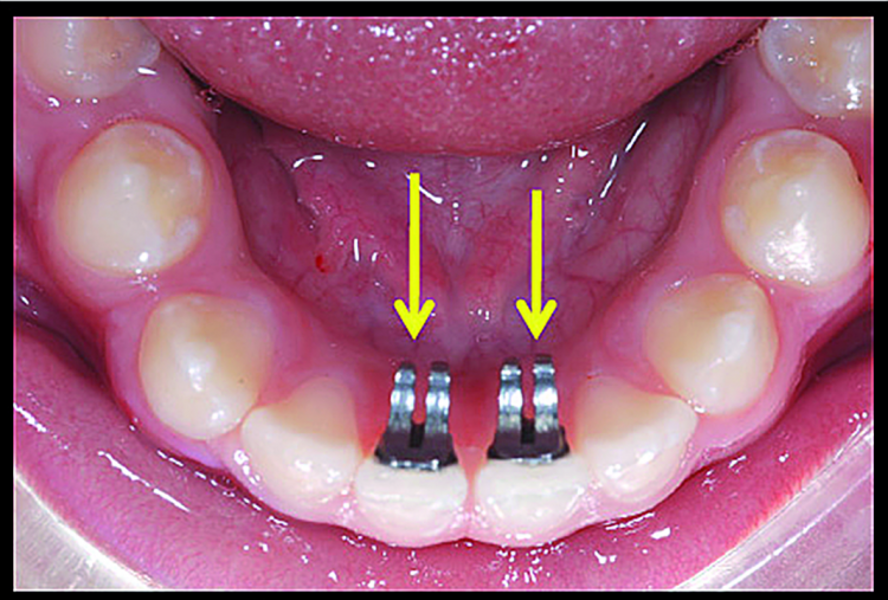

BiTurbo2 system for rapid deep overbite correction